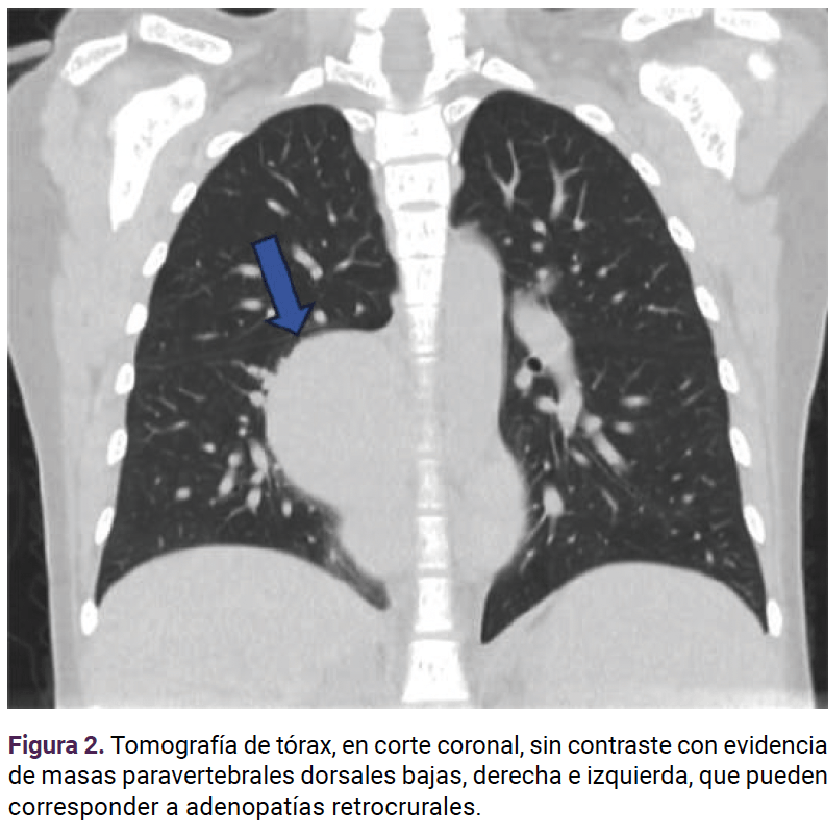

En otra radiografía de tórax se documentó una imagen nodular parahiliar derecha sin borramiento de la silueta cardiaca (Figura 1). Se solicitó una TAC de alta resolución que reportó: masas paravertebrales dorsales bajas a derecha e izquierda quizá correspondientes a adenopatías retrocrurales y nódulo calcificado, en la base del lóbulo superior derecho. Figura 2

<strong>Figura 1</strong>

Figura 1